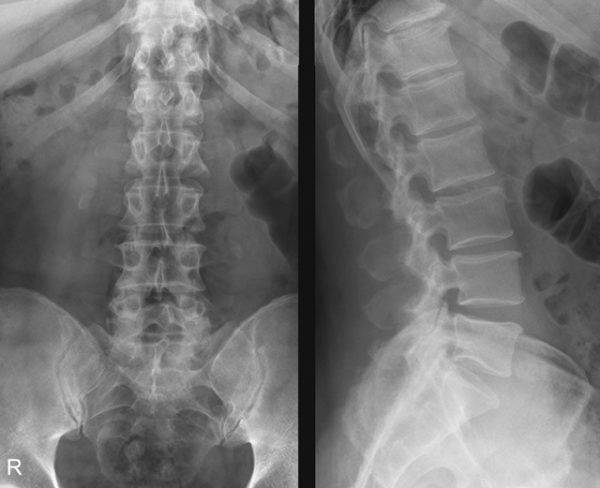

Прежде всего, стоит назвать его основное отличие от рентгеноскопии. Наука не стоит на месте, в том числе и медицинская, старые технологии устаревают, а на смену им приходят новые. Проблема в том, что рентген, как метод диагностики, давно и безнадежно устарел. Он используется по инерции, «по старинке» и совершенно не показывает таких результатов как УЗИ, притом, что вреда от рентгена (хоть и опосредованно) может быть больше.

Рентген как метод обследования устарел и уступает УЗ-диагностике

В результате рентгена образуется черно-белая картинка, которая позволяет увидеть довольно мелкую детализацию, но радиационное облучение при этом попадает прямо в человеческий организм. И доза его варьируется в зависимости от того, какой по площади участок тела необходимо диагностировать. Позвоночник обычно занимает большую площадь, поскольку редко исследуется одна его зона, обычно облучению подвергаются как минимум две (например, шейно-грудная или пояснично-крестцовая). Поэтому рентген нельзя делать беременным и тем, кто кормит грудью, а также имеющим почечную недостаточность пациентам. Способ с применением ультразвука не имеет таких противопоказаний и ограничений.